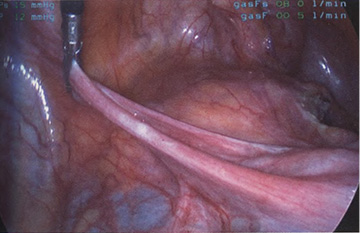

Если оставить в стороне эти достоинства и недостатки, то техника лапароскопической гистерэктомии фактически идентична технике лапаротомической гистерэктомии. В самом начале операции, если она выполняется лапароскопическим методом, необходимо осмотреть всё операционное поле, воспользовавшись для этого панорамным обзором (рис. 12-33—12-37). Операцию начинают с коагуляции и пересечения круглых связок, чем обеспечивается доступ к широкой связке (рис. 12-38—12-40). Брюшину, переходящую с купола мочевого пузыря на переднюю поверхность матки, вскрывают. Пузырь отсепаровывают от матки острым путём (рис. 12-41). После этого вскрывают задний листок широкой связки, а затем принимают решение, оставлять или удалять яичники. Если принято решение оставить яичники, то коагулируют и пересекают собственные связки яичников и маточные трубы (рис. 12-42). Если принято решение удалить яичники (то есть выполнить сальпингоофорэктомию), то с обеих сторон выполняют диссекцию мочеточников от воронко-тазовых связок, которые затем отсепаровывают, коагулируют и пересекают (рис. 12-43). Затем ткань широкой связки отделяют от маточных сосудов (отпрепаровывая их), изолировав, таким образом, мочеточники от маточных сосудов (рис. 12-44 А). Восходящие ветви маточных сосудов коагулируют справа и слева, а затем пересекают (рис. 12-44 Б, В).

Рис. 12-33. А. Лапароскопический вид матки на месте (in situ). Б. Увеличенное изображение матки и образований широких связок.